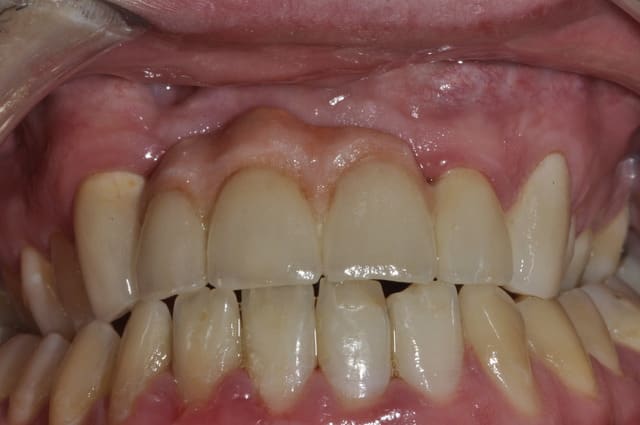

J'ai revu le patient au bout d'un an.

Hygiéne approximative mais pas évidente en même temps.

Je vous ai mis des photos du labo, puis 1 semaine après la pause et enfin celles de la semaine dernière.

On constate des petites zones inflammatoires au niveau des piliers et une légére perte d'attache sur la 23.

Photo prise juste après le détartrage, mais n'excuse pas tous.